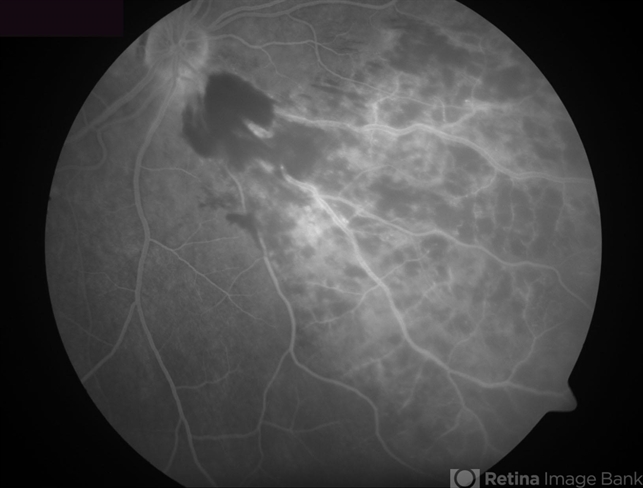

- Inferonasal Branch Retinal Vein Occlusion

- branch retinal vein occlusion (BRVO), vascular incompetence, intraretinal hemorrhage

- Fluorescein angiogram showing hypofluorescence secondary to intraretinal hemorrhages, and perivascular hyperfluorescence secondary to vascular incompetence.